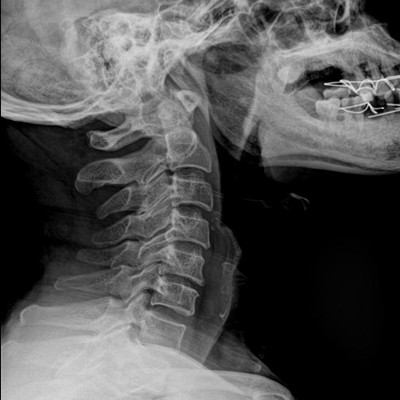

●大尺寸非晶硅平板探測器。

●探測器可以大范圍轉(zhuǎn)動,大尺寸有效探測面積,可滿足人體多部位攝影需求。